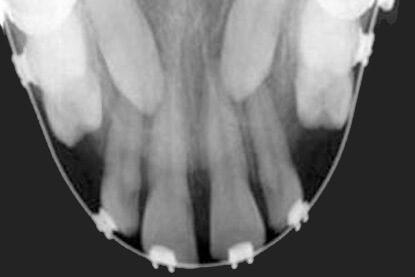

أنواع الأشعة السينية للأسنان:

العض

أوكلوسال